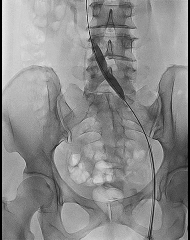

2、导管导丝配合通过病变段后建立导丝路径,依次选择Atlas Gold 12*60mm、Atlas Gold 14*60mm对髂静脉逐段逐级扩张,扩张过程中见明显切迹。

3、扩张结束后,送入Venovo髂股静脉支架 14*120mm,先大滚轮缓慢释放,便于支架近心端的定位,避免过多进入下腔静脉,遮挡对侧髂静脉开口。当近心段充分锚定后,通过小滚轮将整个支架进行完整的释放。

4、再次造影,支架形态良好,髂静脉狭窄解除,髂静脉回流较术前明显改善,髂内静脉返流消失,周围侧支减少。